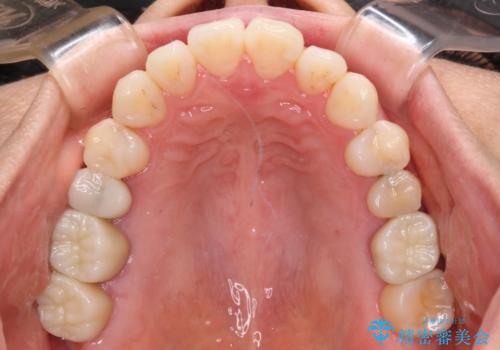

気になる前歯をインビザライン・ライトで 矯正治療後には銀歯をセラミックに

- 捻れた前歯と目立つ銀歯を気にして来院された患者様です。

歯列不正は軽微であったため、インビザライン・ライトにて改善することとしました。

インビザライン・ライトによる矯正治療であったので、時間をかけずに治療を終えることができました。

口を開ける度に目立っていた銀歯もセラミックで自然な口元の印象となりました。